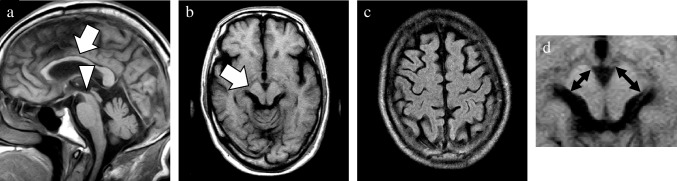

In addition, the presence/absence of subcortical white matter hyperintensity (SWMH) was visually evaluated on axial FLAIR images [ref. 24, ref. 25]. Considering that hyperintensity in the periventricular and deep white matter can be attributed to aging and cerebral small vessel disease (i.e., leukoaraiosis), signal changes confined to the subcortical white matter were exclusively evaluated (Fig. 3).